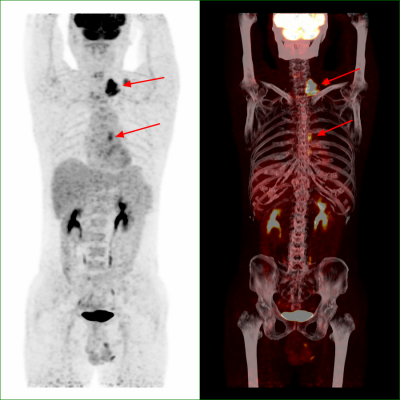

近期,在外务工的市民何先生无意间发现自己左颈部出现有肿块,随后去到当地医院检查,超声提示其左颈部有一个4.9厘米×2.9厘米的包块,彩超提示为:双侧颈部多发淋巴结。为得到进一步诊断和治疗,何先生选择回到了自贡,在市四医院进行PET/CT检查提示为食管癌伴颈部纵隔淋巴结转移。随后,医务人员为其进行胃镜下活检,明确为食管鳞癌。病情得以明确后,何先生在市四医院得到了妥善的治疗。